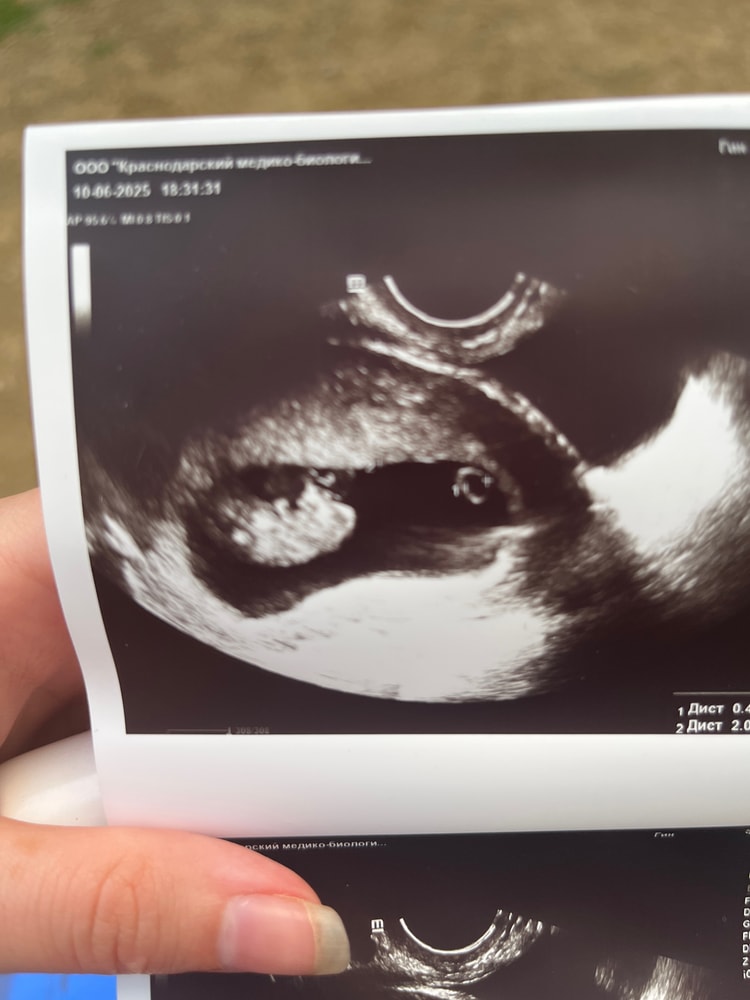

До 15-16 недель «явное выпирание» есть и у мальчиков, и у девочек. Называется половой бугорок. Визуально различается лишь угол наклона, и то, в некоторых случаях невозможно точно сказать пол. В 9 недель его определить нереально. В 12-14 часто ошибаются, а у вас ребенок около 3 см ещё. Изображение

Сомневаюсь, что на таком сроке возможно увидеть пол...Половые органы малыша уже присутствуют, но разглядеть пол проблематично.

Даша, я была на платном узи, возможно хорошее оборудование , да и врач сказала что хорошо видно и я на фото вижу прям вот будто мальчик, тем более скоро скрининг ,там подтвердят( хотя надеюсь разубедят; я хотела девочку 🥲) Изображение

Виктория Алисëнок, у вас там просто половой бугорок. Но о поле еще речи вообще не может быть.